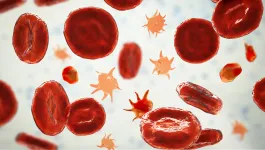

La fisiopatología de la púrpura trombocitopénica trombótica (PTT) se fundamenta en una disminución de la actividad de la proteasa ADAMTS13. La PTT se caracteriza por episodios agudos y puede estar asociada con manifestaciones subagudas y complicaciones crónicas a largo plazo.